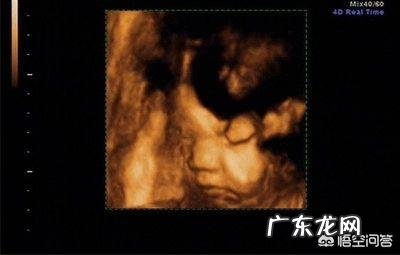

1、什么是四维彩超

四维彩超是世界上最先进的彩色超神设备,主要是采用3D超声图像加上时间维度参数,能够实时获取三维图像,能够显示腹中胎儿的实时动态活动图像 。能够检查出胎儿的发育情况,筛查先天疾病,例如胎儿的唇腭裂、四肢发育畸形、脑膜膨出、脊柱裂、腹壁裂等 。

一般而言,四维检查最佳时间是孕20~28周 。因为这一阶段是胎儿大脑发育的高峰期,这时候胎儿的各器官逐渐发育完善,胎儿大小及羊水适中,在母亲子宫内的活动空间比较大,胎儿胎儿骨骼回声影响比较小,图像也比较清晰 。